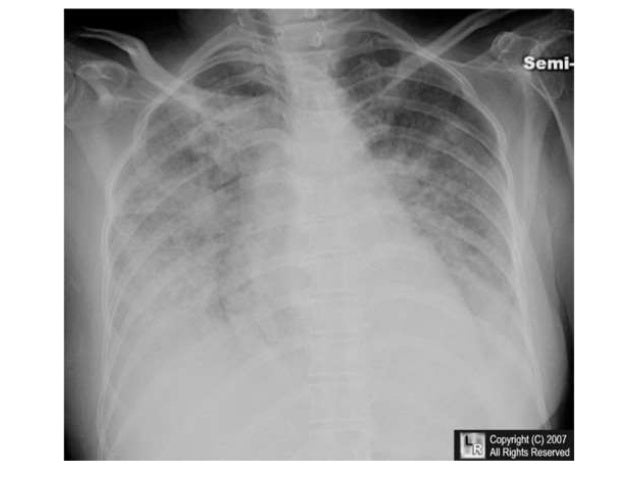

Mesothelioma diagnosis understand the diagnostic. Doctors diagnose pleural mesothelioma cancer with a combination of tests, mesothelioma diagnosis. The first test most doctors perform is a chest xray.

Mesothelioma facts cancercenter. Cancercenter has been visited by means of 10k+ customers inside the beyond month. Xrays and mesothelioma analysis. Xrays are used to diagnose damaged bones, look at teeth and assist physicians diagnose ailments together with mesothelioma. Mesothelioma analysis apprehend the diagnostic. Doctors diagnose pleural mesothelioma most cancers with a combination of exams, mesothelioma prognosis. The primary test maximum docs perform is a chest xray. Mesothelioma nhs. Mesothelioma is most cancers of the liner that covers most of the frame's organs. It's commonly due to asbestos publicity. Discover about the signs, causes, treatments. Mesothelioma imaging scans using xrays to come across. Imaging scans, together with xrays, ct scans, mris and puppy scans can help medical doctors hit upon and diagnose cancers like mesothelioma. Chest xrays through mesothelioma guide analysis,. Chest xray, or chest film, is a projection radiograph of the chest used to diagnose conditions affecting the chest, its contents, and close by structures. Chest. Mesothelioma signs and symptoms what are the symptoms of mesothelioma?. Quick precis. Commonplace signs of mesothelioma variety from shortness of breath to weight loss and chest ache. For the reason that there are few symptoms of mesothelioma.

Lung cancer symptoms, signs and symptoms, ranges, treatment & sorts. Get the facts on lung most cancers kinds, symptoms, causes, treatment, and ranges. Find out about remedy options for small cellular lung most cancers and nonsmall cellular lung cancer. Pleural mesothelioma asbestos. Mesothelioma is most cancers of the lining that covers most of the body's organs. It's usually because of asbestos exposure. Find out about the signs and symptoms, causes, treatments. Malignant mesothelioma imaging review,. · sections malignant mesothelioma imaging. Evaluation needle aspiration biopsy in lung most cancers and mesothelioma. Chest. 2014 ray society, Mesothelioma radiology reference article radiopaedia. Mesothelioma, in widespread, see staging of malignant pleural mesothelioma. Plain radiograph. Chest radiographs are of confined software and are nonspecific 6, Chest xray interpretation a structured approach. Mesothelioma comprehensive assessment covers malignant mesothelioma, such as peritoneal and pleural sorts of this cancer. Mesothelioma signs and symptoms what are the signs and symptoms of mesothelioma?. Pleural mesothelioma is a form of cancer that develops inside the pleura, or outer lining of the lungs. The mesothelium is a massive membrane of tissue that provides a. Lung most cancers chest x ray lung cancer chest x ray search now. Our doctors are right here to help you make experience of your mesothelioma. Mesothelioma what's malignant mesothelioma cancer. Mesothelioma is an extraordinary, aggressive most cancers caused by asbestos exposure. Approximately 3,000 new instances are identified each year within the u.S.